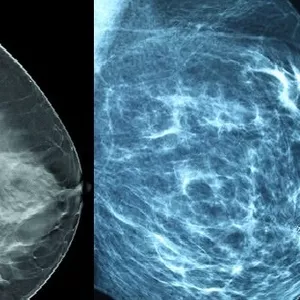

Imagem do curso TOMOSSINTESE E AVANÇOS TECNOLÓGICOS EM MAMOGRAFIA 🔗 Acesse o Curso Oficial

CURSO TOMOSSINTESE E AVANÇOS TECNOLÓGICOS EM MAMOGRAFIA APRESENTAÇÃO O curso tem como objetivo abordar a TOMOSSINTESE e os avanços tecnológicos em mamografia, além de um conhecimento vasto sobre a evolução diagnóstica. CONTEÚDO 1 - BOAS VINDAS 2- APRESENTAÇÃO 3 - MAMOGRAFIA CONVENCIONAL 4 - MAMOGRAFIA DIGITAL 5 - TOMOSSÍNTESE 6 - ULTRASSOM DAS MAMAS 7 - MAMOGRAFIA COM CONTRASTE 8 - BIÓPSIA DAS MAMAS 9 – ENCERRAMENTO 10 - MATERIAL DIDATICO Módulos do Curso 10 CARGA HORÁRIA 10h PROFISSIONAL ALTAMENTE QUALIFICADO PROF. ELISANGELA SENRA MENDES Pós Graduação em Mamografia e Controle de Qualidade Pós Graduação em Imaginologia pela Universidade Nove de Julho Graduada em Tecnologia em Radiologia pela Universidade Nove de Julho Técnica pelo Colégio São Camilo. Trabalha na Medicina Diagnósticos como Técnica em Mamografia, Raios-x e Densitometria óssea. Docente em nível superior. MATERIAL DIDÁTICO Adquirindo o curso você terá acesso ao material completo sobre os avanços tecnológicos em mamografia. PDFs VÍDEOS E DOCUMENTÁRIOS JOGOS LINKS DA ÁREA DA RADIOLOGIA RDC Nº 330 Grupo WhatsApp Exclusivo do Curso Duvidas com o Suporte da Equipe do PortaldaRadiologia.com VANTAGENS CURSO EM EAD Aulas Gravadas possibilitando assistir quando você quiser Facilidade de Estudar pelo celular, computador ou Tablet Estudar no seu ritmo e no tempo que você acha melhor CERTIFICADO O Certificado Digital é emitido com 10h (carga horária) referente as vídeos aulas e materiais disponíveis para download. O certificado do curso é emitido logo após a conclusão do curso. LIBERAÇÃO DO CURSO O curso será liberado logo após a confirmação do pagamento verifique no e-mail cadastrado ou acesse a plataforma. O curso ficará disponível por 1 ano (365) dias após a confirmação do pagamento, passando este período o curso irá expirar. QUALQUER DÚVIDA ENTRE EM CONTATO: WhatsApp 📲 11 94675-4398 E-mail: 📧 portaldaradiologia@yahoo.com